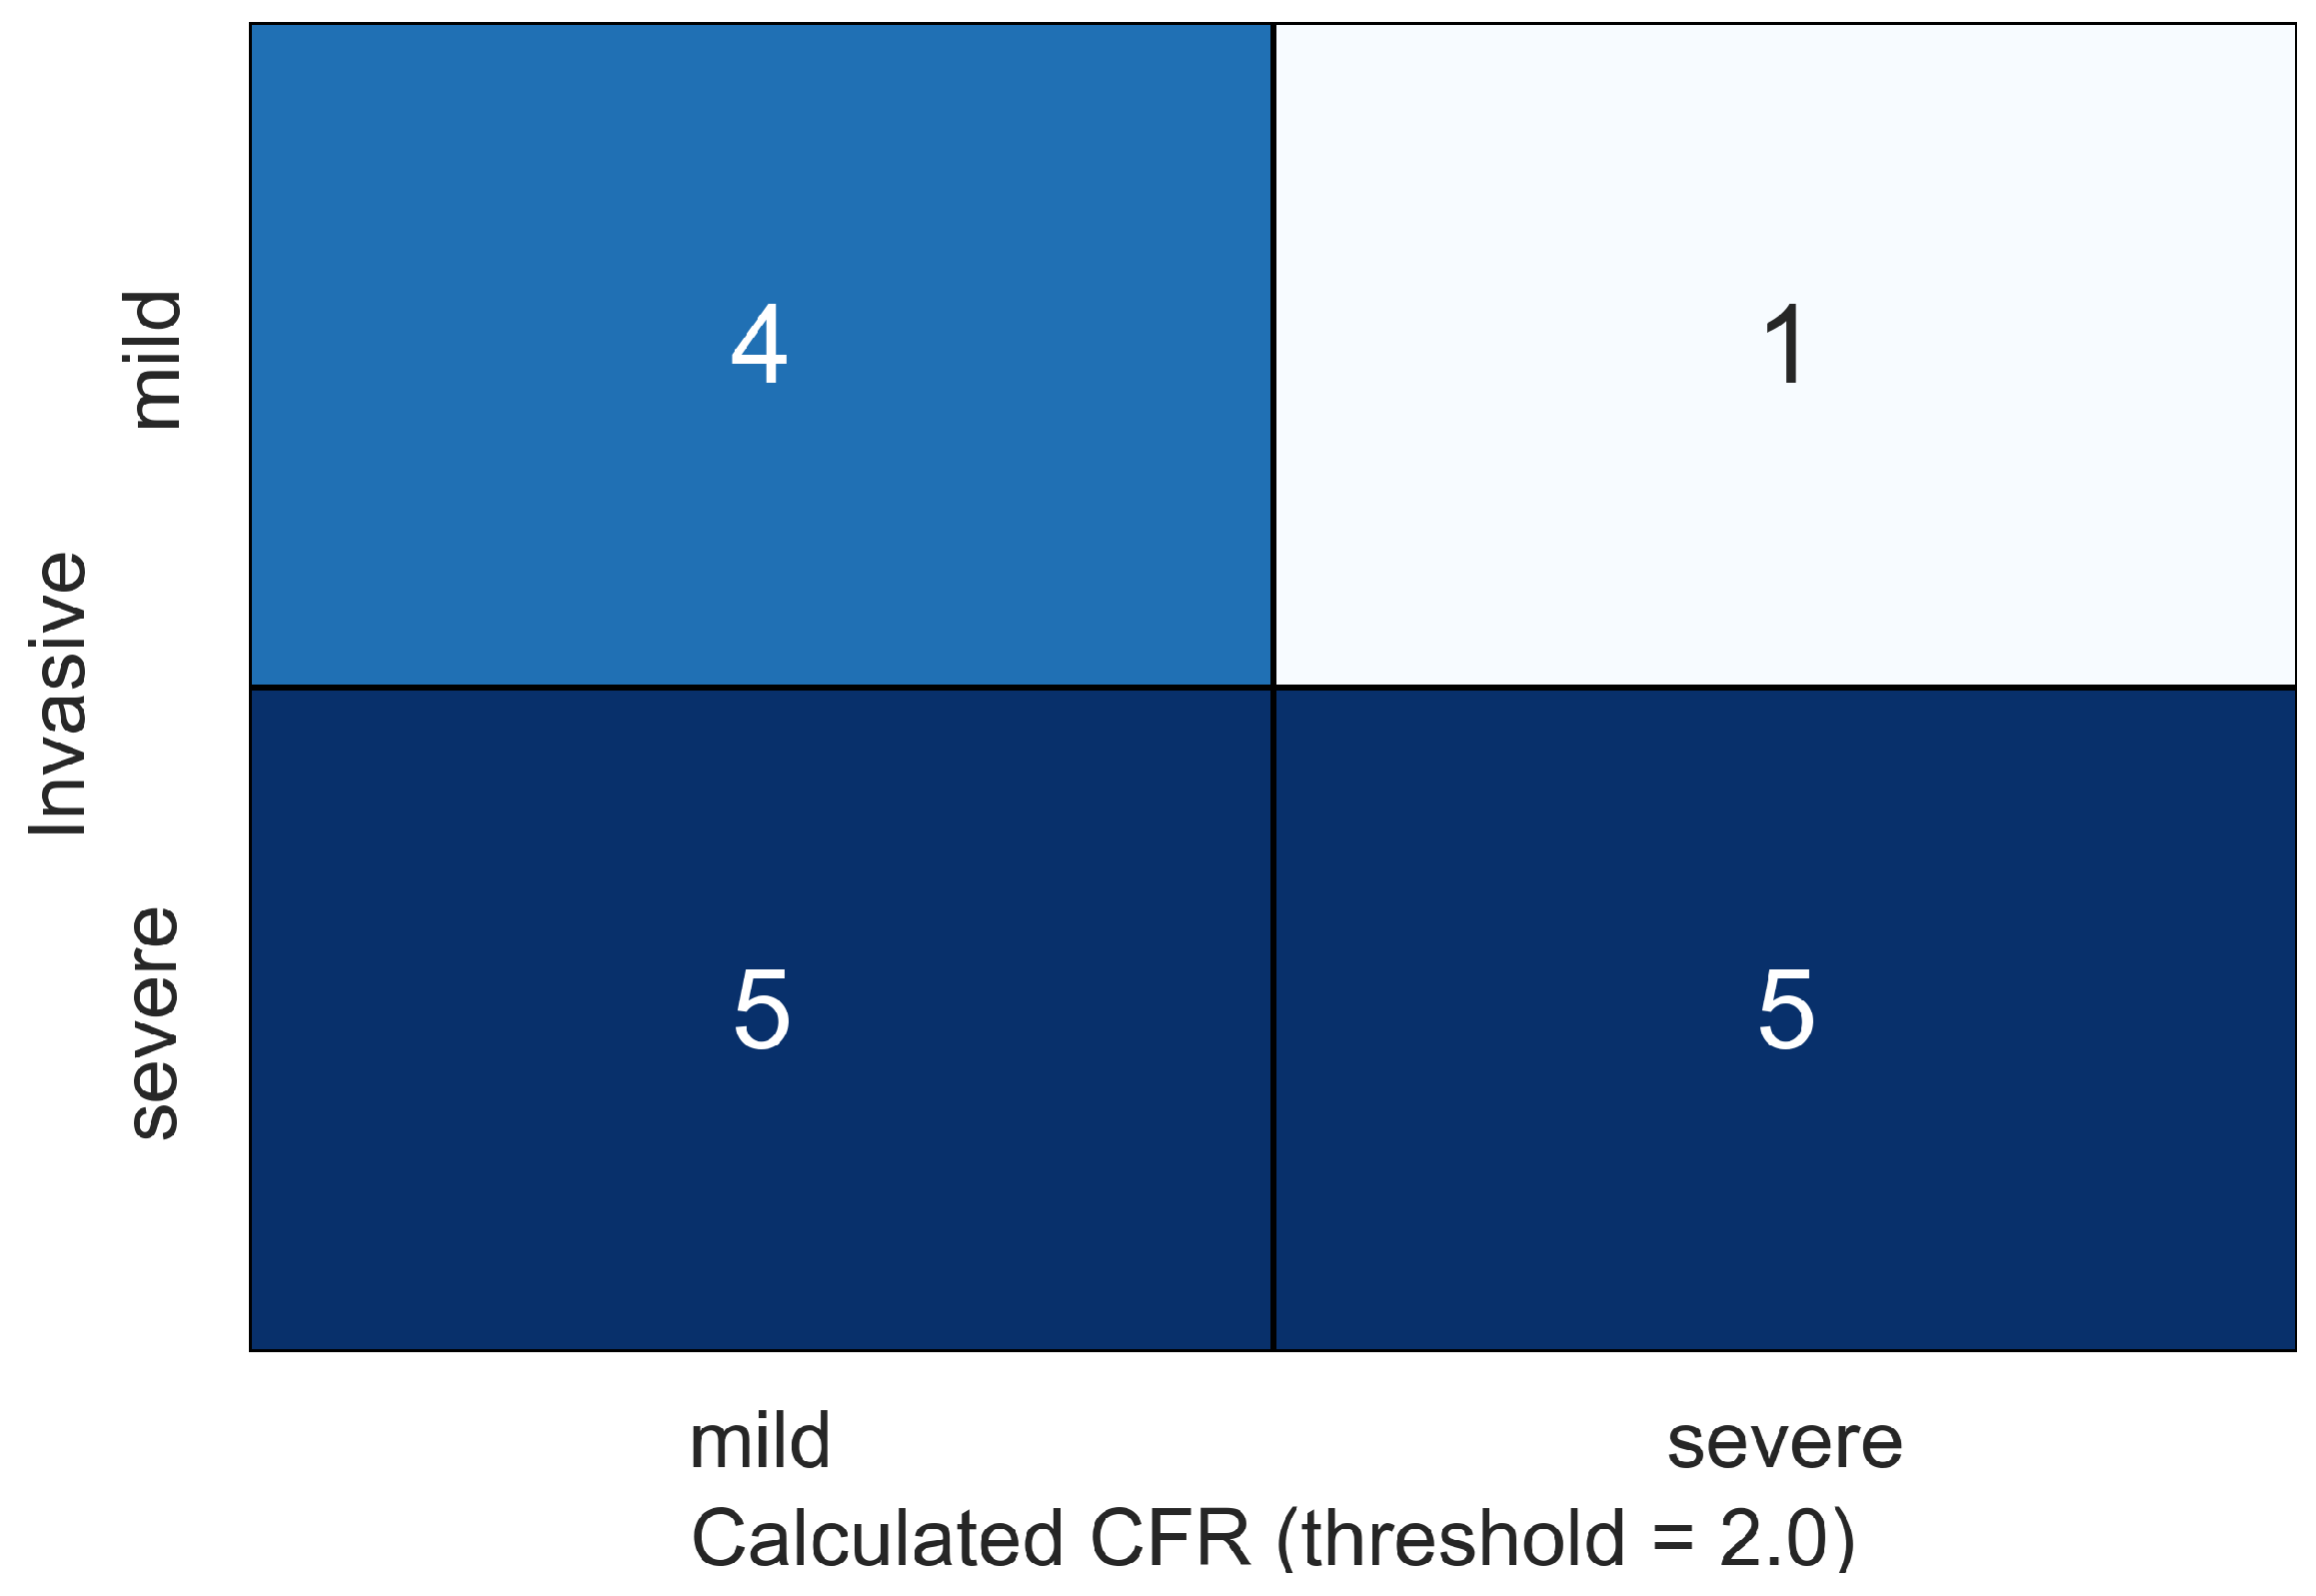

4. Results

5. Discussion